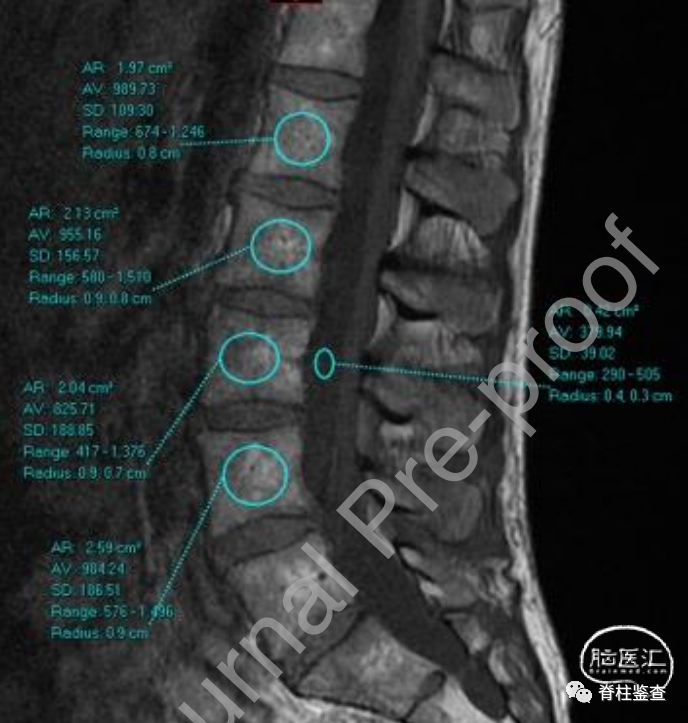

基于早期研究,骨质疏松的骨骼以骨小梁萎缩和局部脂肪细胞替代为特征,随着骨质疏松发生,脂肪渗入增多,在MRI T1上呈现更高的高信号。因此,作者试图创建一个基于MRI的评分来评估椎体骨质量(vertebral bone quality,VBQ),并评估其与DXA的相关性。

1、在L1-L4椎体的髓质部和L3水平的脑脊液间隙内设定感兴趣区

2、记录每个感兴趣区内的平均信号强度(Signal intensity,SI)与脑脊液的平均信号强度

3、椎骨的平均信号强度除以脑脊液的平均信号强度即为VBQ